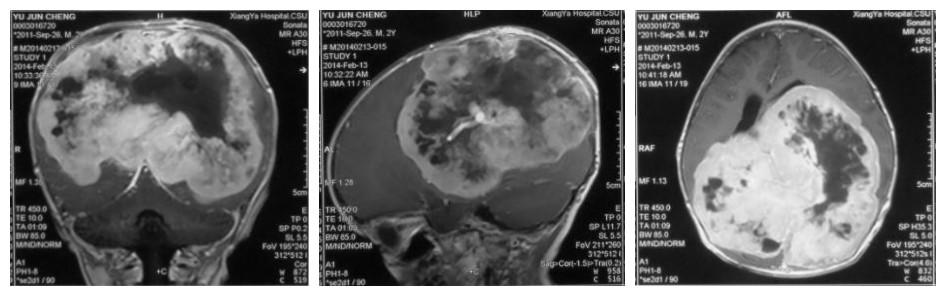

术前影像资料

患者余天(化名),今年2岁,2013年9月出现“头围增大、行走不稳”等情况。随后,患者被父母带至广东省某大型医院求医。行头部磁共振检查发现:患者颅内巨大占位,肿瘤组织占据了整个颅内约2/3的空间,将正常脑组织压缩至原来的1/3。经查体后诊断为:颅内巨大脑膜瘤。患儿因年龄较小,耐受性较成人好,但各种高级中枢、脑干已严重受压,颅内情况已达临界点,随时有可能出现昏迷,甚至呼吸、心跳停止。

正当患者父母几乎绝望的时候,有朋友推荐中南大学湘雅医院神经外科。2014年2月,患者一家来到湘雅医院,找到了小儿神经外科主任刘景平教授。刘景平教授在对患儿详细的病史询问、体格检查,并仔细阅读了患儿的磁共振结果后认为:患者可以手术,但其颅内脑膜瘤体积巨大、血运丰富,加之患者本身年龄小,手术风险极大。“术中若稍有不慎,便可引发患者肢体活动障碍,偏瘫等后遗症,重则意识障碍、昏迷,危及生命”。